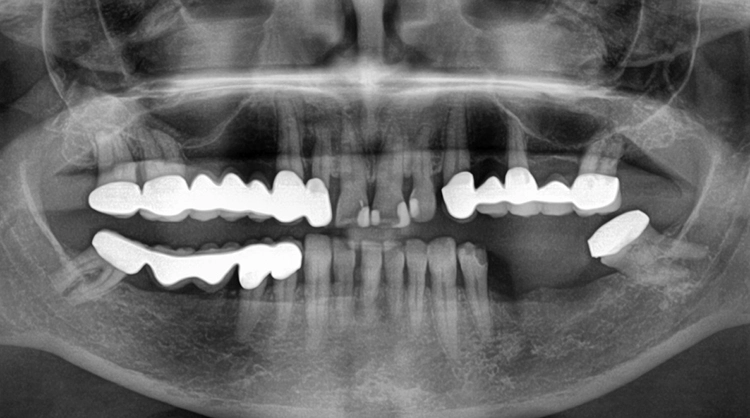

Eine 63-jährige Patientin stellte sich mit einer schon seit längerer Zeit bestehenden Schaltlücke im Unterkiefer links vor. Ziel der geplanten Behandlung war die adäquate prothetische Neuversorgung mittels einer implantatgetragenen Brücke (Abb. 1).

Die Verschraubung stellt eine wichtige Prävention gegen das Auftreten einer Periimplantitis dar. Das röntgenologische Abschlussfoto zeigt die knöcherne Regeneration des Defektes und gute Osseointegration der Implantate (Abb. 21).